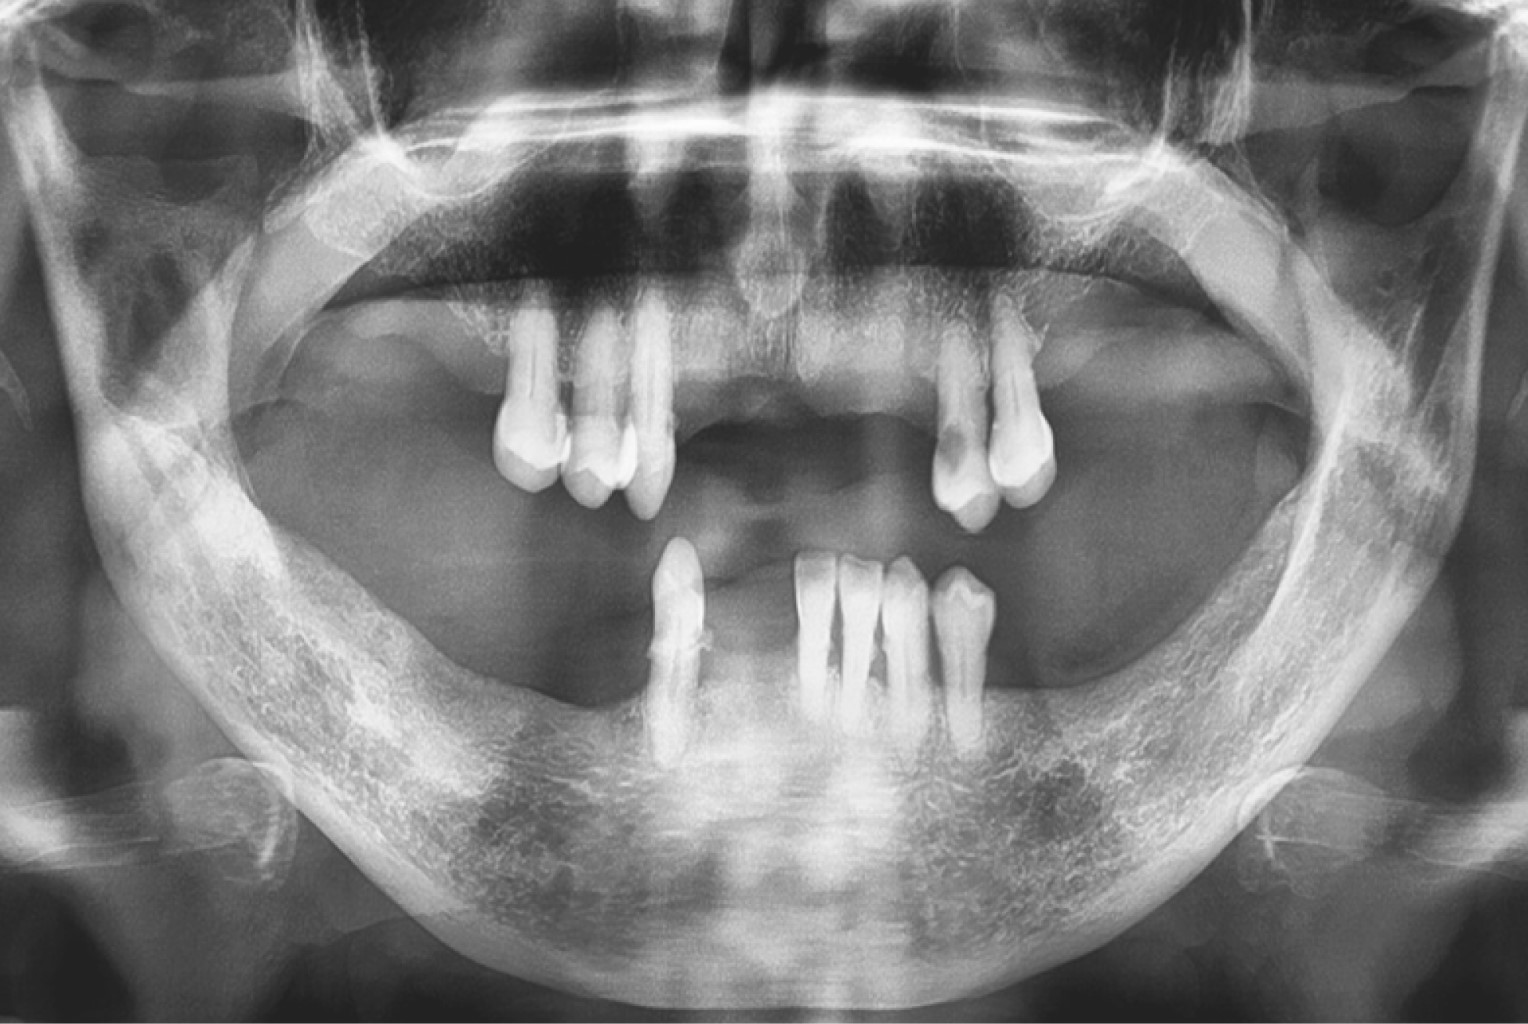

Heterotopic third molars are teeth that are embedded in the maxilla and mandible, remote from their usual eruption site. Its etiology is not well defined and there are various theories at the moment. These teeth can appear in different areas of the bone's structures, having a predilection for the jaw. They usually appear between the second and seventh decade of life, and in most cases are imaging findings. The mandibular third molar is the tooth with the most frequent heterotopia, being its usual location in the mandibular branch and in the subcondylar region. The dentigerous cyst is the most common associated pathology. We present a case of a long evolution heterotopic third molar in the right mandibular branch, related to a dentigerous cyst which was managed under local anesthesia. The etiology, surgical technique and special considerations related to heterotopic teeth are described.

Figure 3